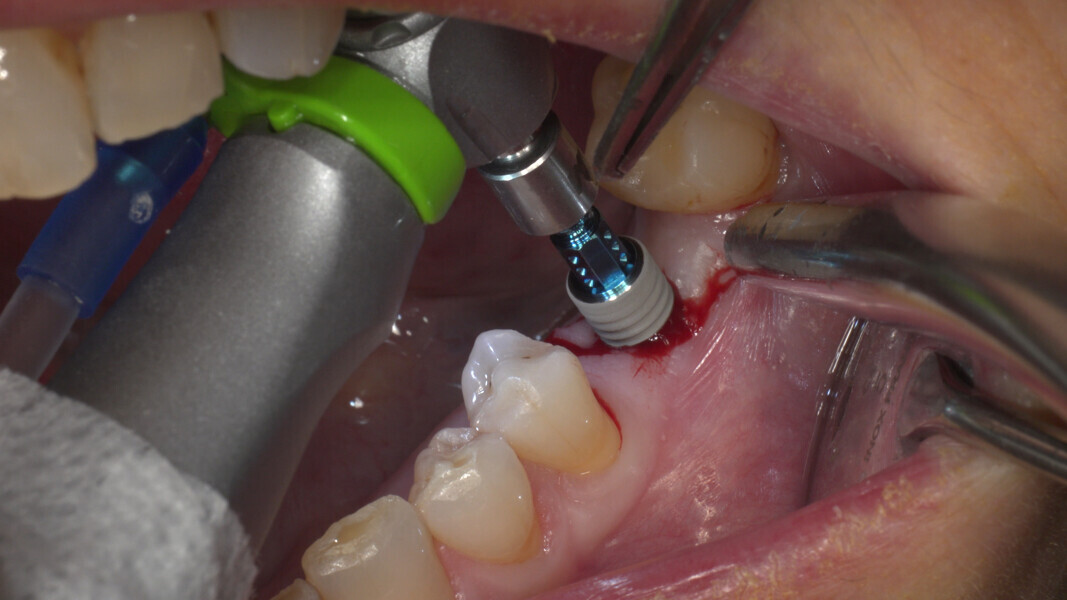

Conventional and immediate loading with final n!ce screw-retained crowns